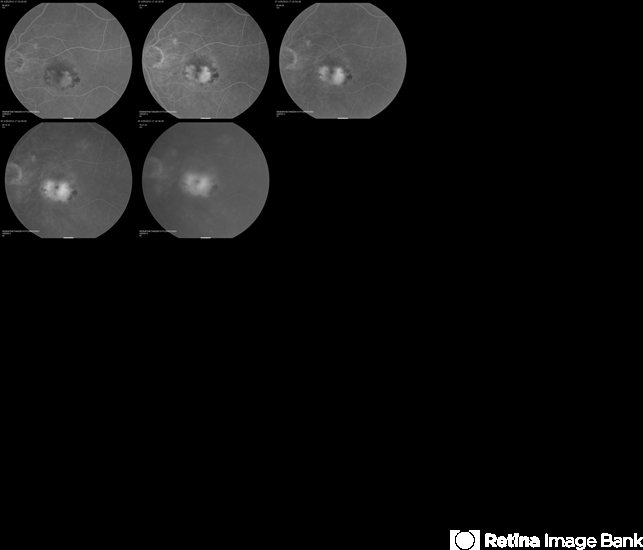

- choroidal neovascularization (CNV), classic form

- Classic CNV.